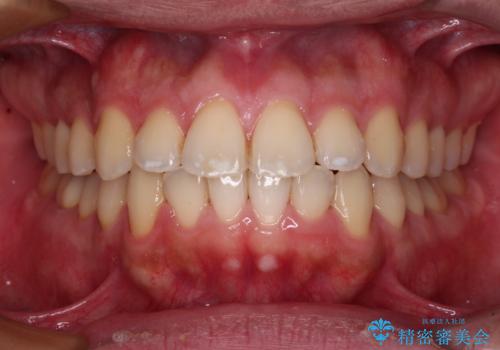

- 治療期間

- 9ヶ月

- 前歯のデコボコを治したいとのことで来院された患者様です。

できる限り楽して、短期間で治したいとのことで、ワイヤー装置にて矯正治療を行うこととしました。